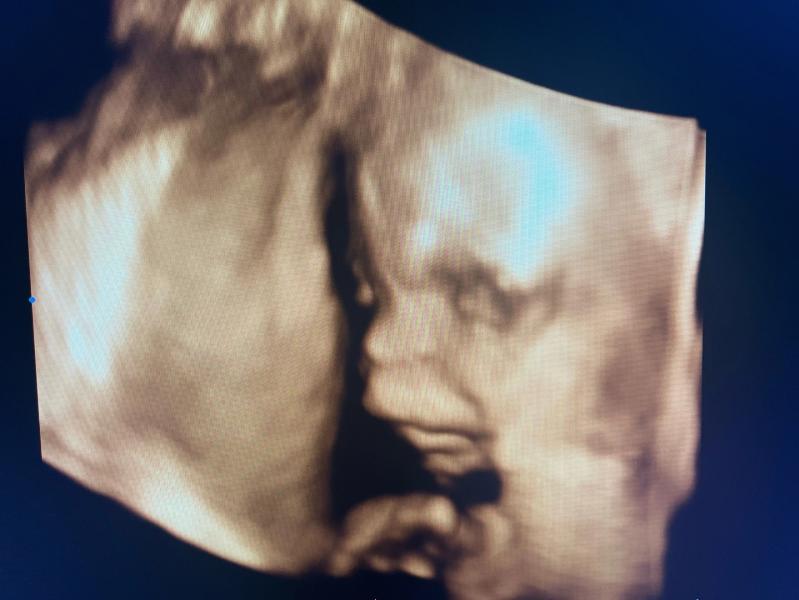

Мне кажется или наш сын вылитый папа? 🫣

Носишь, носишь, а они потом все вылитые папы …